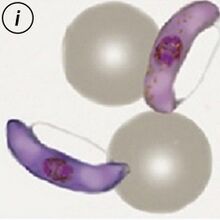

The gametocyte

The sexual replication in P.falciparum is very distinctive and may be the only form visible (particularly of after treatment).

- male and femaie gametocytes have the appearance of rods although these may be distorted

- The rod shapes may become curved by the red cell membrane to give the characteristic "banana" form”

- The residual membrane (empty of haemoglobin) is often seen as a "blister" to one or both sides of the parasite

- The single chromatin area is in the centre of the parasite, often has pigment overlying it

P.falciparum gametocytes